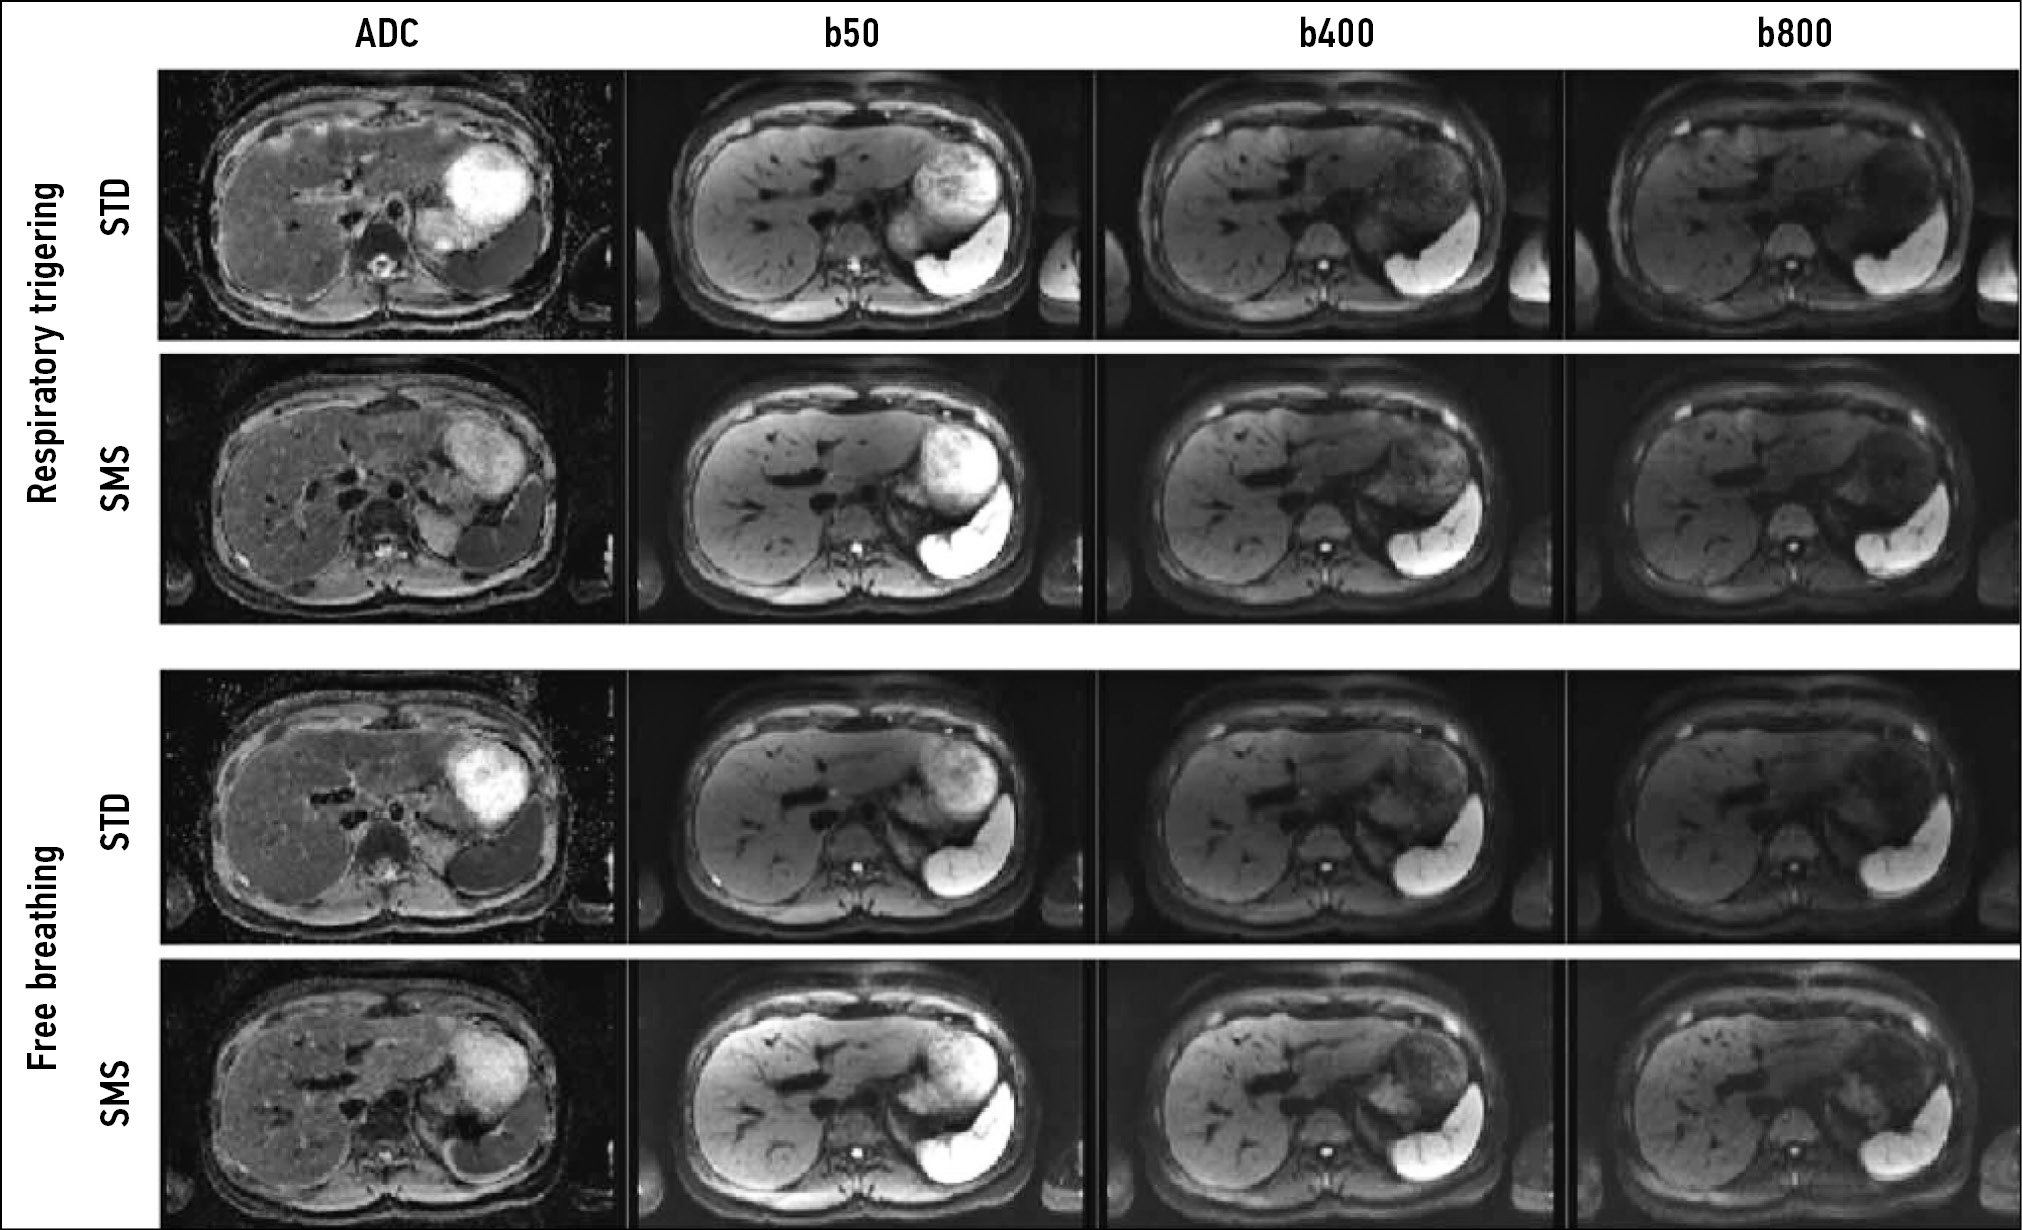

DWIs are widely used in abdominal radiology. The most common are single-shot echoplanar sequences with or without breath-holding. Parallel data acquisition is used to reduce scan time and more accurately calculate the apparent diffusion coefficient, and modern techniques allow for taking DWIs with high spatial resolution in <1 min (simultaneous multislice imaging DWI) [16] (Fig. 9).

Figure 9. Comparison of standard (STD DWI) and simultaneous (SMS DWI) multislice diffusion-weighted images with free breathing and respiratory triggering using various b-factors (50, 400, and 800 s/mm2) and corresponding apparent diffusion coefficients. The mean scan time was 10:30 min (5:56–18:13) for STD DWIs and 3:29 min (2:19–4:27) for SMS-DWIs [16].